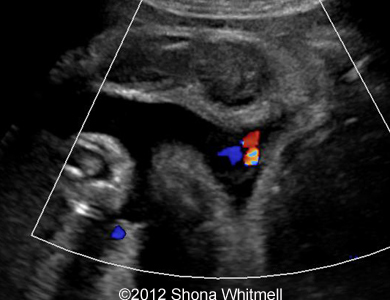

Figure 2

: 3-vessel cord and 2-vessel cord at the same plane.

Image-21